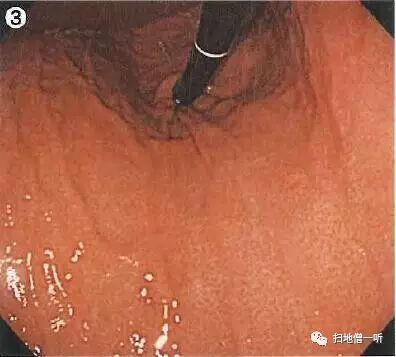

靛胭脂染色后表面光滑,未见凸凹变化

NBI观察周围粘膜呈褐色改变,边界不甚清晰。